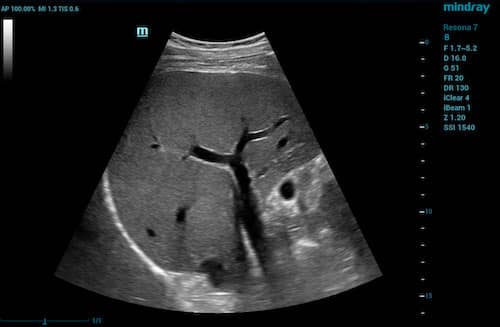

A convex transducer is a curved transducer. The shape of a convex transducer determines the sector width and shape of the image. A convex transducer offers a wider field of view for larger or deeper structures. Convex transducers are most frequently used for abdomen, obstetrics/gynecology (OB/GYN), urology, and some musculoskeletal (MSK) applications.

2D image of liver visualized with a convex transducer